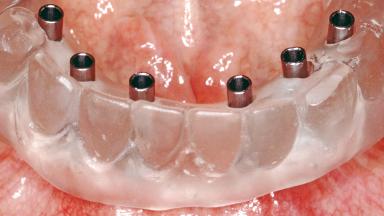

Conventional Loading of Six Implants in the Mandible and Final Restoration with a Full-Arch Metal-Ceramic FDP

A 68-year-old, completely edentulous male patient presented for evaluation and treatment options. He reported excellent general health and was taking no regular medication. He had been edentulous for approximately 12 years, having lost his teeth to periodontal disease and dental caries. The patient’s chief complaint was incompetent function. His secondary concerns included his appearance and the desire for a predictable outcome. He attributed his reduced functional capacity to his lower complete denture, which he described as poor. He was particularly concerned with the denture’s instability and poor fit. In general terms, he was satisfied with the maxillary complete prosthesis. The maxillary prosthesis was characterized by adequate retention, stability, and support, although the fit was considered less than ideal.

# of Implants 6

Type of Implants One-Piece

Attachment One-Piece

Prosthesis Type FDP

Defining Characteristics Fully edentulous lower jaw to be rehabilitated with an implant-borne fixed dental prosthesis

Retention Screw-retained, with 4 or more splinted implants Screw-retained, with 4 or more splinted implants